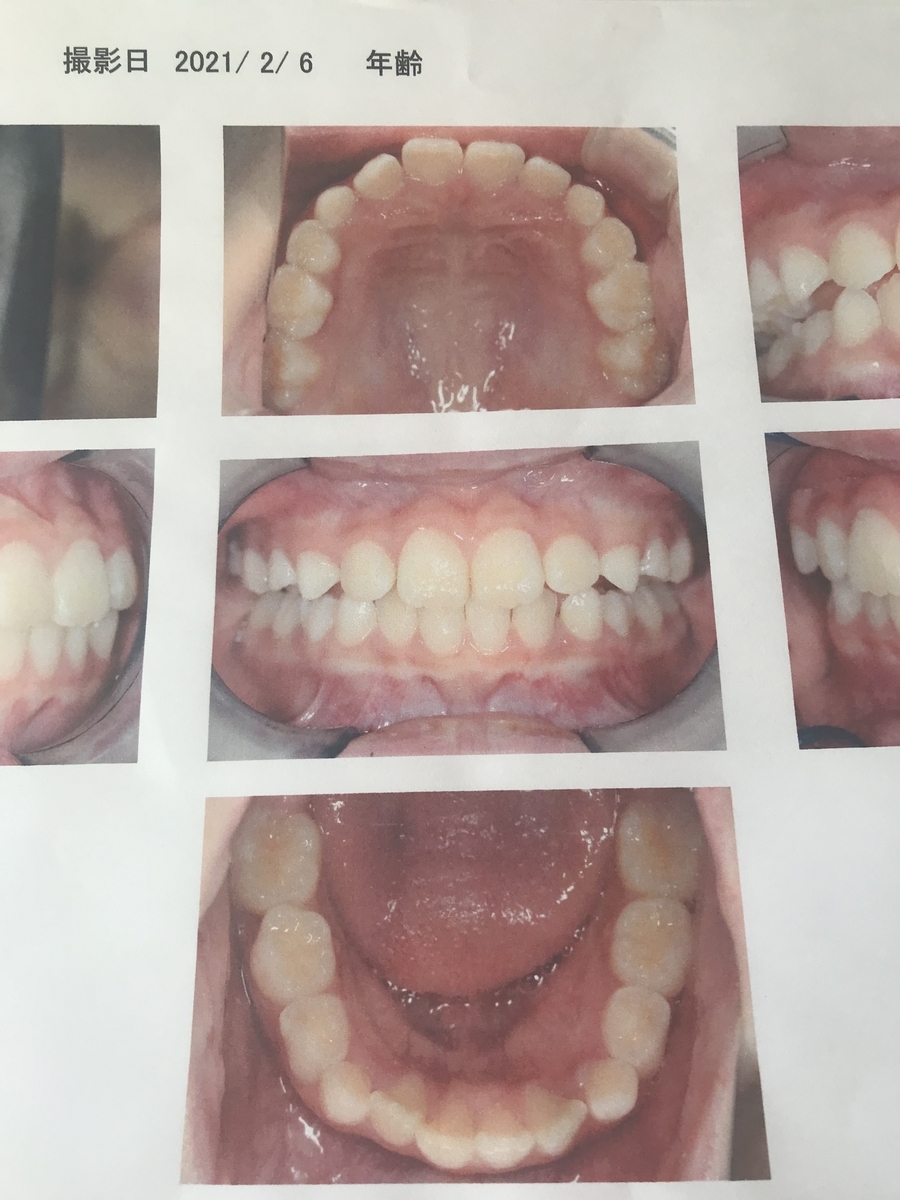

2021年2月(3年生)

1年後、だいぶ揃ってきていますね。ですがまだ永久歯はこれから生え変わりますから気が抜けません。

十分に永久歯が生えるスペースを空けておかないといけないそうです。